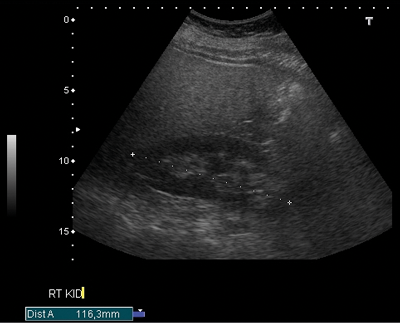

Figure 3a: US shows bar of cortex traversing the expected renal sinus fat.

Figure 3b: CTU shows two ureters exiting the left kidney.

Duplex kidney

Duplex kidney (Figure 3) has an incidence of 0.3-0.6% [8] and consists of two pelvicalyceal systems draining a single renal parenchyma. The two pelvicalyceal systems may have either a single or bifid ureter (partial duplication) or a double ureter draining each collecting system separately into the urinary bladder (complete duplication). In 20% the contralateral ureter is also duplicated. Complete duplication results in an ectopic ureter which inserts outside of the bladder trigone. Eighty-five percent of these ectopic ureters obey the Weigert-Meyer rule. This states the upper pole ureter inserts ectopically inferomedially to the orthostatic lower pole ureter, often with a ureterocoele.

The ureterocoele can cause obstruction of the upper moiety ureter, and also distort the orthostatic insertion of the lower moiety ureter causing reflux. In 15% of complete duplication cases, the upper moiety ureter inserts anywhere along the ectopic pathway [3]. In men, if this is outside of the bladder, the upper moiety ureter insertion is always above the external sphincter and so urinary continence remains, however in women the ectopic upper moiety ureteric insertion is below the sphincter, resulting in urinary incontinence. There is a heavy female predominance (M:F 1:10), which may also be due to the condition resulting in urinary incontinence in some women causing increased symptomatic presentation.

US is used for screening, and shows a band of renal parenchyma traversing the renal sinus fat. Two central echo complexes with intervening renal parenchyma demarcate the duplex system. However, US may fail to enable differentiation between a bifid renal pelvis from a bifid ureter or from two complete ureters [4]. The best imaging of the duplex system is shown on CT urogram which clearly demonstrates ureteric anatomy. On CT there are fewer calyces and infundibula of the lower moiety collecting system, and a shortened upper pole infundibulum. On axial slices the ‘faceless kidney’ sign can aid diagnosis, this is when no renal sinus or collecting system is seen at the junction of upper and lower pole of the duplex kidney [9].